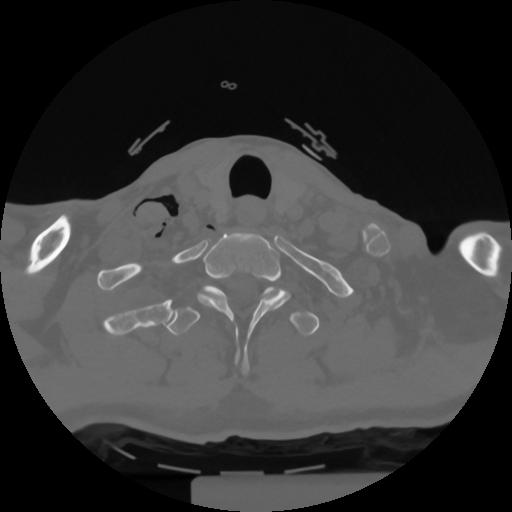

12 P.BLANDAS,,Vol,0.5,P.BLANDAS,,